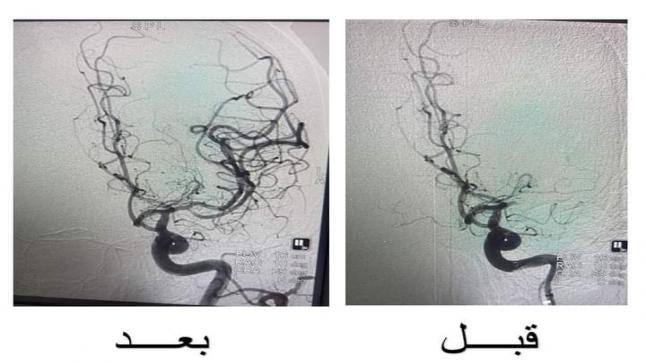

حيث اثرت الجلطة الدماغية على النطق لديها بالاضافة الى ضعف حاد في الجزء الايمن من الجسم، وتم الاتصال مع طوارىء المستشفى التخصصي وحضرت المريضة خلال أقل من ساعة من بدء حدوث الاعراض، وتبين من الصورة الطبقية وجود انسداد كامل في الشريان السباتي الايسر والشريان الأوسط الدماغي وتم تشخيصها بجلطة وتم تفعيل stroke code (رمز الجلطات الدماغية) وبدء الاجراءات بشكل سريع، وتم نقل المريضة الى قسم القسطرة، حيث قام الدكتور حازم حبوب استشاري الاشعة التداخلية ومعالجة الجلطات الدماغية مع الفريق الطبي والتمريضي بإجراء عملية سحب الخثرة خلال مدة زمنية قصيرة جداً (عشرين دقيقة) وضمن بروتوكول الاعتمادية الدولية لوحدة الجلطات الدماغية للمستشفى التخصصي.

وقد تكللت العملية بالنجاح وتعافت المريضة خلال 48 ساعة بشكل تام وعادت لممارسة حياتها الطبيعية، وتقدمت بالشكر الجزيل للفريق الطبي ولإدارة المستشفى التخصصي على سرعة الاجراءات والاستجابة في مثل هذه الحالات.